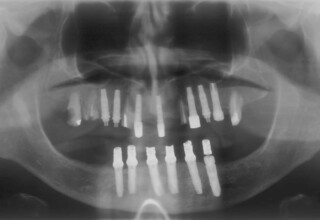

Ολική Στοματική Αποκατάσταση σε Εμφυτεύματα με διαφορετική προσέγγιση στην Άνω και Κάτω Γνάθο

Κάτω γνάθος: εξαγωγές, άμεση τοποθέτηση εμφυτευμάτων και άμεση φόρτιση(την ίδια ημέρα) με προσωρινή γέφυρα

Άνω γνάθος: σταδιακές εξαγωγές, σταδιακή τοποθέτηση εμφυτευμάτων και σταδιακή ενσωμάτωση τους στην προσωρινή γέφυρα ώστε η ασθενής να μην μείνει ούτε μια ημέρα χωρίς αποκατάσταση. Στόχος η συνεχής λειτουργική και αισθητική αποκατάσταση της ασθενούς χωρίς άμεση φόρτιση των εμφυτευμάτων λόγω ανατομικών ιδιαιτεροτήτων.

Χρησιμοποιήθηκαν παλαιές χαμογελαστές φωτογραφίες της ασθενούς γιατί είχε χαθεί τελείως το φυσικό σχήμα των δοντιών εξαιτίας των πολλαπλών προσθετικών προσπαθειών που είχαν γίνει στο παρελθόν. Μεταφέρθηκε στην προσωρινή γέφυρα η σχέση των φυσικών δοντιών μεταξύ τους άλλα και με τα χείλη. Δοκιμάστηκε η φώνηση και η μάσηση με δυο διαφορετικές προσωρινές άνω γέφυρες και εκτιμήθηκε η αισθητική απόδοση τους. Αφού επιτεύχθηκαν σε βαθμό ικανοποιητικό η φώνηση και η αισθητική εμφάνιση της οδοντοφυΐας, η προσωρινή αποκατάσταση χρησιμοποιήθηκε ως οδηγός για την τελική.